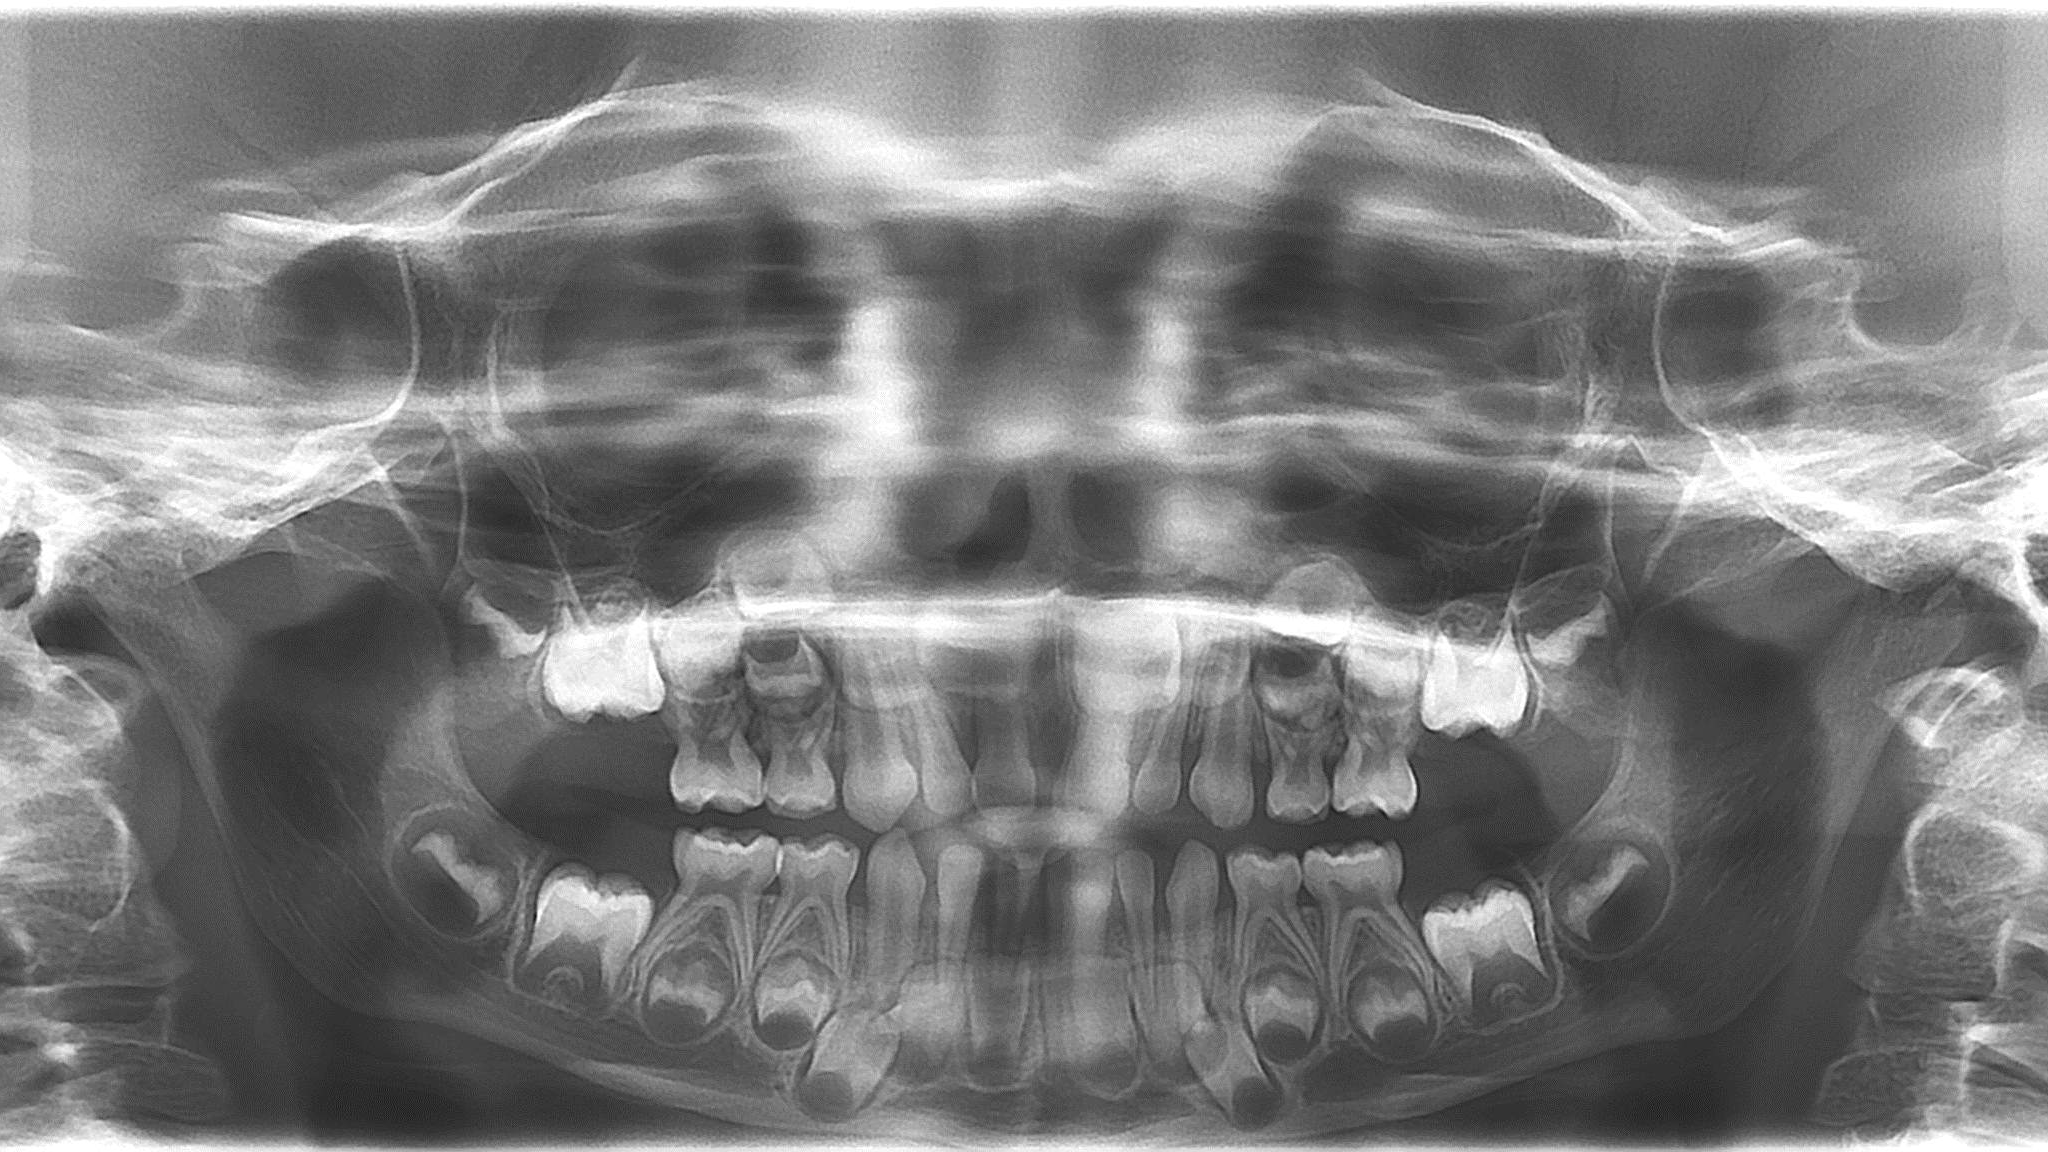

bilan des radiographies début et en cours de traitement

surveillance évolution de la dentition